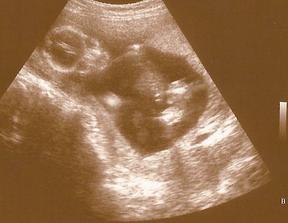

Naše milá rozrůstající se rodinka :o))

Začalo to v dubnu 1999 a zpečetili jsme to nejdříve narozením našeho syna Adámka a poté svatbou 1.10.2005, za chvíli budeme mít první výročí 🙂